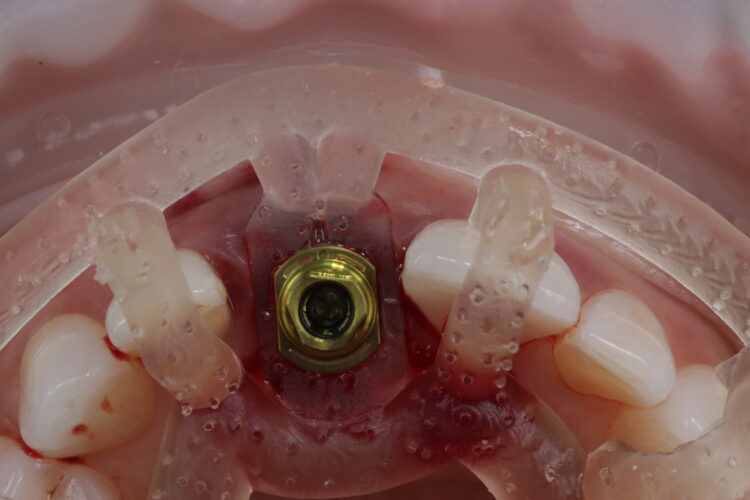

The CONELOG® Progressive-line implant maximised primary stability and in this case the implant was inserted at 70Ncm. The pre-made temporary was used as the temporary restoration; however, there would also be the option of modifying the existing crown.

The implant was placed in close contact with the palatal bone, 1mm below the buccal bone height. A temporary cylinder abutment was connected, with flowable composite placed to attach the temporary restoration. The composite resin was used to create the optimal emergence profile ensuring a highly polished restoration in the transition zone.

A bone graft was then performed, adding MinerOss® Blend (BioHorizons Camlog) to the jump gap. This affords an ideal combination of cortical and cancellous bone, delivering high bone density and reliable revascularisation to ensure the fast and predictable turnover of bone.